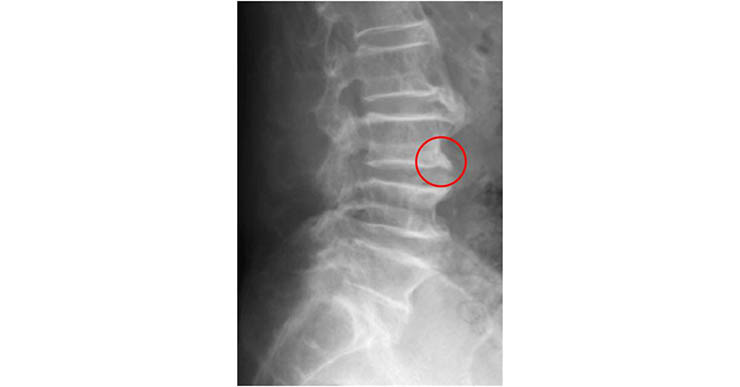

反過來說,長在脊椎前側這麼大一坨骨刺基本上是不會有任何感覺的(如下圖)